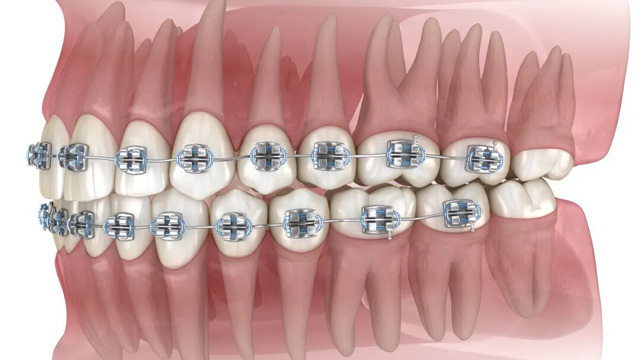

02智齿阻挡正畸牙齿移动

正畸治疗中,医生会根据诊疗方案,让牙齿沿着预设轨迹移动(比如前牙内收、后牙调整咬合等)。比如需要内收前牙改善凸嘴时,智齿的存在会“顶住”后牙,导致牙齿无法顺利移动到理想位置。这种情况,可能需要拔除智齿来为排齐牙齿提供必要的空间。

而正畸治疗期间需要定期复诊、调整矫治器。如果智齿反复发炎,不仅会让你承受疼痛,还会耽误正畸进度。